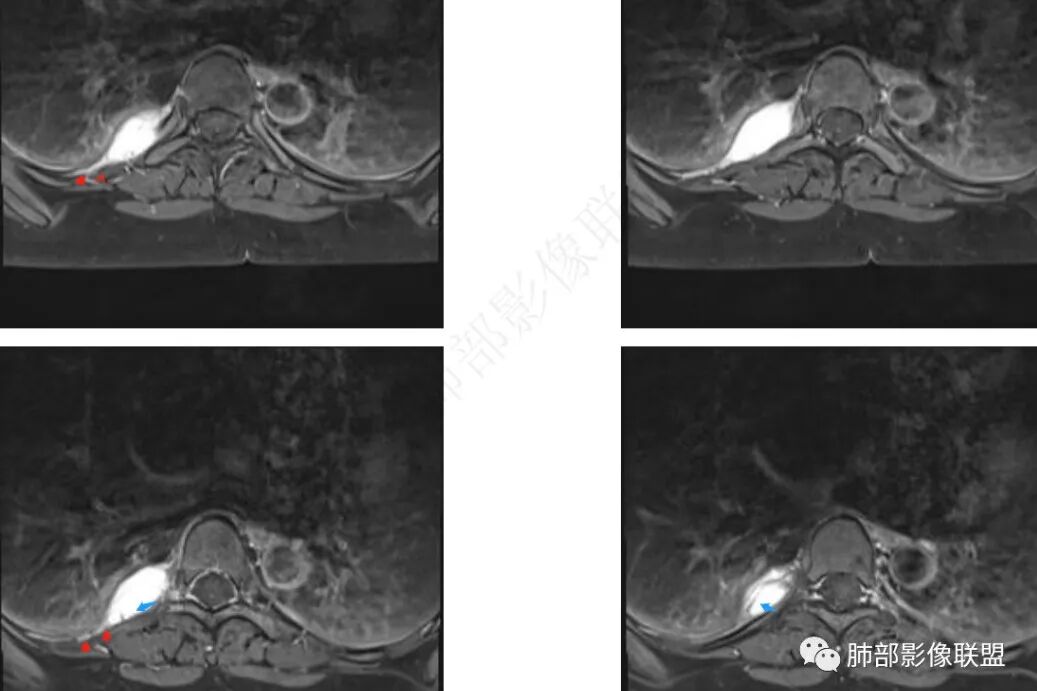

MRI表现:病灶多呈长T1长T2信号影,T2WI脂肪抑制序列呈高信号具有特征性,有时可显示流空血管影,弥散多不受限,增强后强化方式多样,与CT强化类似。

中青年女性,胸痛就诊,CT检查发现右后纵隔占位,病灶位于后胸壁纵隔移行区,略呈卵圆形或梭形蔓延,质地软,等/稍长T1、显著长T2信号,T2W脂肪抑制序列“亮灯”样高信号,这种磁共振信号特征对血管瘤具有强烈提示意义!(实在是太亮了,严格意义上的肿瘤罕见)

病灶显著强化,强化与纵隔大血管相仿且同期,一般会提示是血管源性病变,如血管瘤,如果边缘结节样强化逐渐填充渐进,则提示可能为海绵状血管瘤。